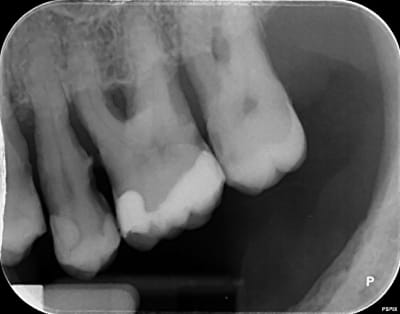

la retro c'est aussi de chez acteon, le pspix2, les erlm sont de chez eux. Que reprochez vous ? Image trop flou ? Vraiment bcp plus flou que chez un concurrent ? Pensez vous que cela vienne des capteurs ou de la machine avec un mauvais reglage de netteté, ou un mauvais réglage tension, intensité,temps exposition ?

Pour les rétro je trouve qu'elles sont pas nettes... moins nettes que la pano.

Peut être que c'est le filtre quand tu exportes les clichés.